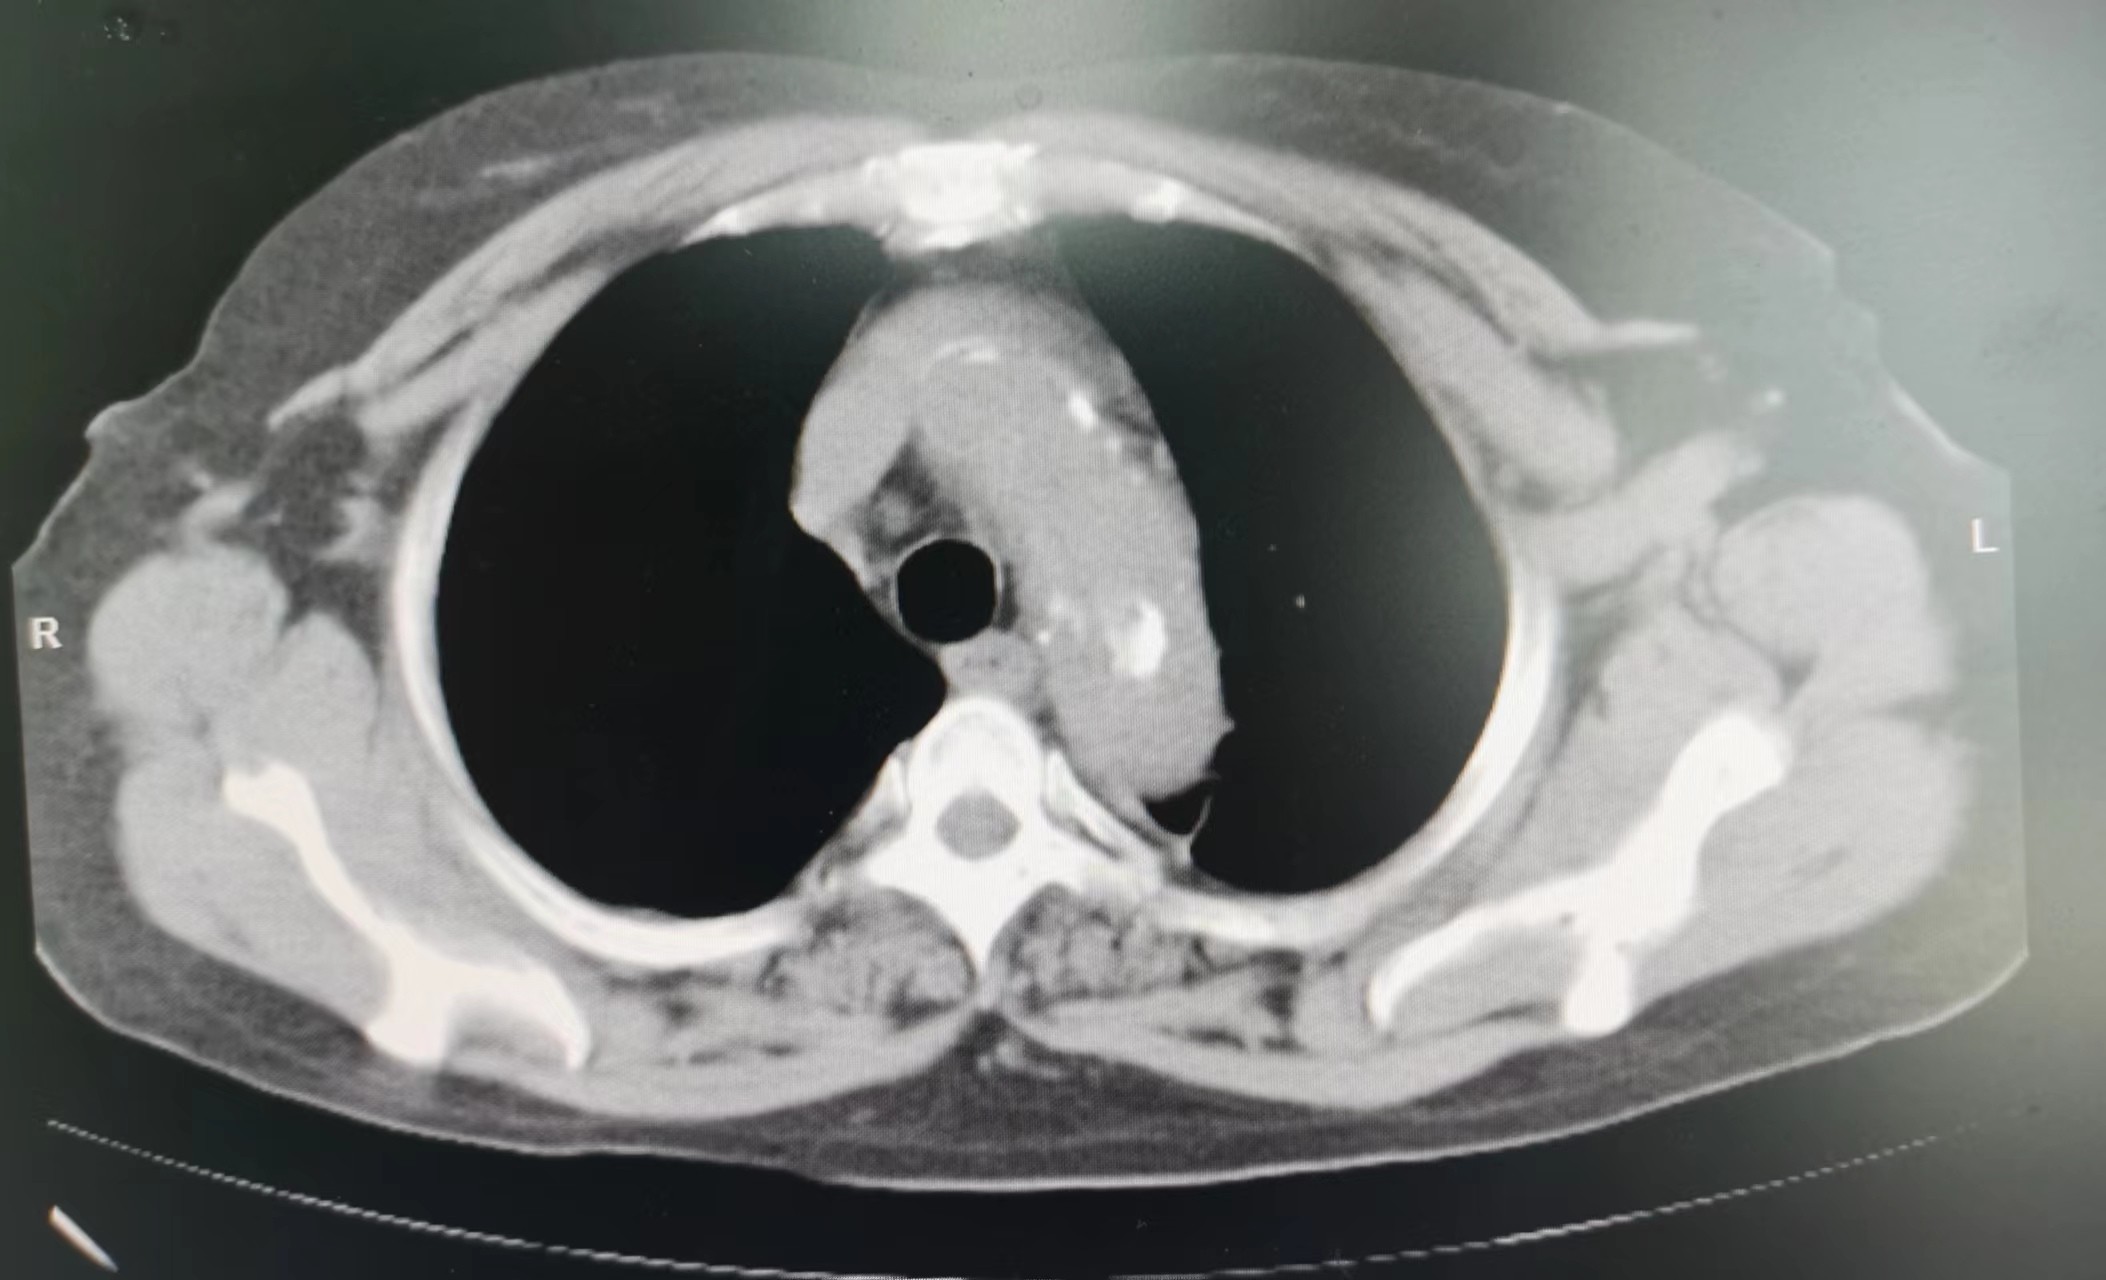

2023年11月,廖阿姨开始出现上腹部不适及胸痛,在外地医院住院治疗,当时查胸部CT考虑为:1.肺纤维化;2.双肺小结节;并经完善其他相关检查后考虑腹痛为:慢性胃炎(未行胃镜检查)。因临近过年,廖阿姨决定回本地过春节,在外地住院治疗10余日后和我院血液净化中心联系透析事宜。2023年12月,廖阿姨在我院透析时仍诉有上腹痛,值班医生经过仔细查体,感觉廖阿姨不像单纯慢性胃炎那么简单。首先,廖阿姨剑突下压痛不明显;其次,廖阿姨腹痛呈阵发性加重,加重时疼痛可累及左侧胸部,严重时胸部疼痛呈撕裂感,这些不像仅有慢性胃炎的症状。我院肾内科主任、主任医师李友河会诊后建议患者住院进一步检查,廖阿姨当日办理了住院。廖阿姨住院期间,肾内科予以相关治疗后其腹痛逐渐缓解,但未完全消失,经李友河主任、主管医生反复沟通和讲解病情后,廖阿姨及其家属终于认识到病情发展的严重性,从原本不愿检查的态度转变为同意完善胸部CT检查。经胸部CT平扫,结果为:1.主动脉夹层可能,建议进一步增强检查;2.右肺、左肺上叶少量慢性炎症;3.主动脉、冠状动脉硬化;4.心包少量积液,左侧胸腔少量积液。

当结果出来后,李友河主任第一时间查看了结果,并马上和患者家属沟通,建议廖阿姨马上行胸部CT增强扫描,同时,我院将立即开通绿色通道,转入我院深度帮扶医院——广东省人民医院进行救治。当晚,廖阿姨胸部CT增强结果提示为主动脉夹层,我院立即派出救护车和医护人员,全程护送廖阿姨至广东省人民医院进一步救治。廖阿姨先后在省人民医院心脏急危重症监护室、心内五科治疗,3日后,省人民医院专家为其行胸主动脉覆膜支架腔内隔绝术+暂时性经静脉起搏器系统的置入等治疗,2024年1月廖阿姨好转出院,并继续预约到本院透析。廖阿姨及家属在省人民医院出院后,十分感激我院及省人民医院的救命之恩,他们认为在省人民深度帮扶我院以来,佛冈县人民医院打出了“省医就在家门口的口号”,不管是佛冈县人民医院的医疗技术,还是医德医风均取得了很大的进步。随后,廖阿姨特地送来了锦旗,感谢全体肾内科医护人员的救命之恩。我院肾内科坚持“以患者为中心”的理念,进一步改善医疗服务,满足患者日常就医需求,为患者提供全周期的诊疗服务,在不断提高诊疗水平的同时,丰富服务内涵建设,改善患者就医体验,为广大群众生命健康保驾护航。科室简介